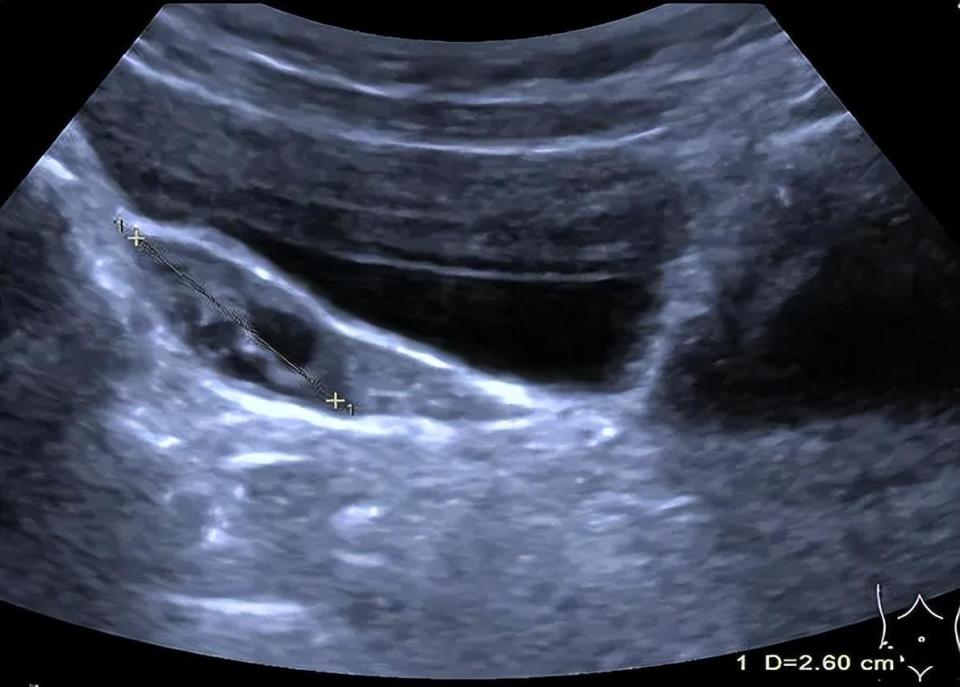

图片

▲彩超下,婷婷的双侧卵巢内见8个直径大于4mm卵泡